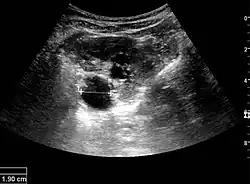

Cortical thickness should be estimated from the base of the pyramid and is generally 7–10 mm. If the pyramids are difficult to differentiate, the parenchymal thickness can be measured instead and should be 15–20 mm (Figure 3). The echogenicity of the cortex decreases with age and is less echogenic than or equal to the liver and spleen at the same depth in individuals older than six months. In neonates and children up to six months of age, the cortex is more echogenic than the liver and spleen when compared at the same depth.[1]

Figure 3. Measures of the kidney. L = length. P = parenchymal thickness. C = cortical thickness.[1]